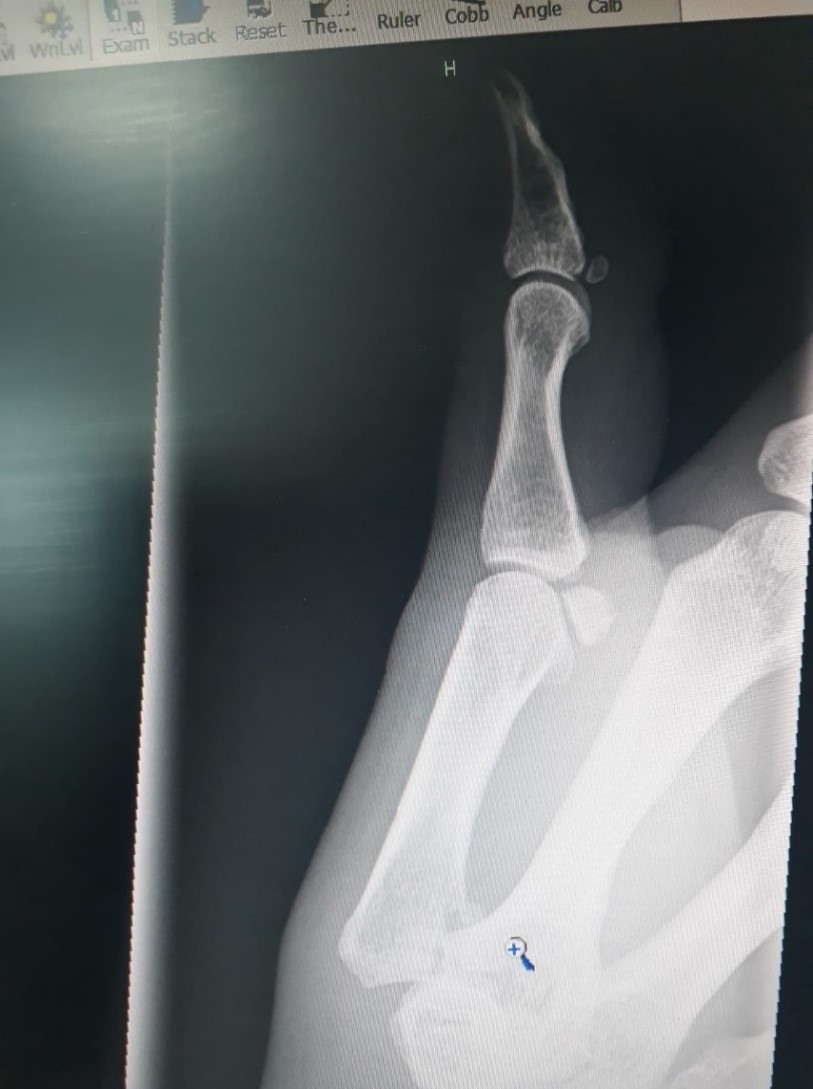

Eventually I was seenThumb x-ray I explained where I had been And the next thing they say Is that I need an x-ray

After more time waiting And much anticipating The pictures were clear And the medic said, ‘Oh dear!’

‘No wonder it’s numb You’ve broken your thumb And your elbow too!’ Now what a to do

So they plastered my armElbow x-ray To keep it from harm Put a splint on my hand As thumb movement was banned